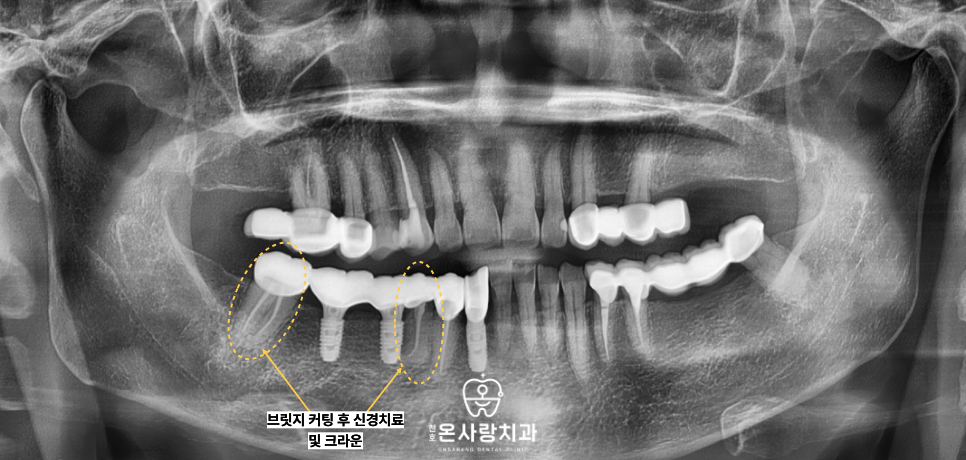

저희는 환자분의 장기적인

저작 기능을 회복하기 위해

기존 브릿지를 절단하고

각 치아의 상태를

재평가하기로 결정하였습니다.

먼저 상태가 매우 좋지 않았던

하악의 앞니 치아는 브릿지를

절단한 이후 발치를 진행하였습니다.

이 자리는 더 이상 자연 치아로서의

기능을 하기 어려웠기에

천호역임플란트를 식립하여

단독적인 지지력을 확보하였습니다.

반면 송곳니 치아는 뿌리와

전반적인 치질 상태가

양호한 것으로 판단되었습니다.

따라서 해당 치아는 무리하게

발치하지 않고 크라운 보철물을

새롭게 제작하여 씌워줌으로써

본래의 기능을 유지하도록 하였습니다.

브릿지의 다른 기둥이었던

작은어금니와 큰어금니의 경우에는

보철물을 제거하고 보니

이차 충치가 진행되어 있었습니다.

보철물 내부에서 충치가 발생하면

환자 스스로가 이를 인지하기 매우 어렵습니다.

이에 따라 오염된 부위를 깨끗하게 제거하고

신경치료를 병행하여 치아의 수명을 연장한 뒤

크라운을 씌워 개별적으로 보호하였습니다.